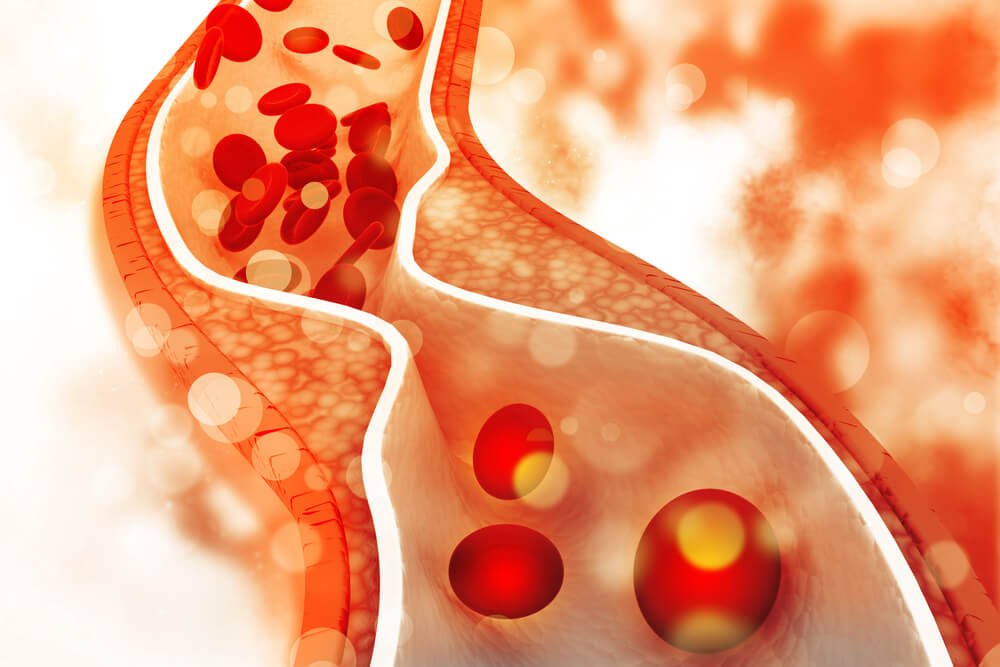

Las enfermedades cardiovasculares se producen en su mayoría por la acumulación de colesterol malo en las arterias. Una persona tiene el colesterol alto cuando tiene niveles iguales o superiores a los 220 mg/dl, y ya está en un estado crítico cuando tiene sus valores superan los 250 mg/dl.

El colesterol es una molécula de grasa esencial para la vida que proviene principalmente de la síntesis que realizan órganos como el hígado y el intestino. Es parte de las membranas celulares y además el precursor de algunas hormonas, ácidos biliares, vitamina D y otras sustancias esenciales para el organismo.

También se puede absorber a través del consumo de alimentos de origen animal. Pero al acumulación de colesterol en las paredes de las arterias es lo que desencadena una reacción inflamatoria, facilitando el crecimiento de las placas de ateroma, responsables de la aterosclerosis, entre otros trastornos.

Esto se vincula además con la tendencia a sufrir infartos de miocardio, accidentes cerebrovasculares y afecciones en el hígado y los riñones.